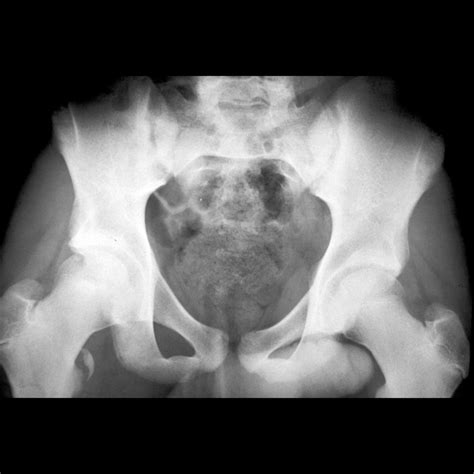

If you suspect an avulsion injury, professional medical diagnosis is vital. Doctors typically use physical examinations and imaging techniques to confirm the diagnosis. An X-ray is usually the first line of defense to visualize the bone fragment. In more complex scenarios, an MRI or CT scan might be ordered to evaluate the extent of soft tissue damage and the exact displacement of the bone.

The severity of an avulsion fracture in hip cases can vary significantly based on how much bone is displaced. While some injuries are minor and involve only tiny bone fragments, others may require surgical intervention to ensure the bone heals in the correct position.